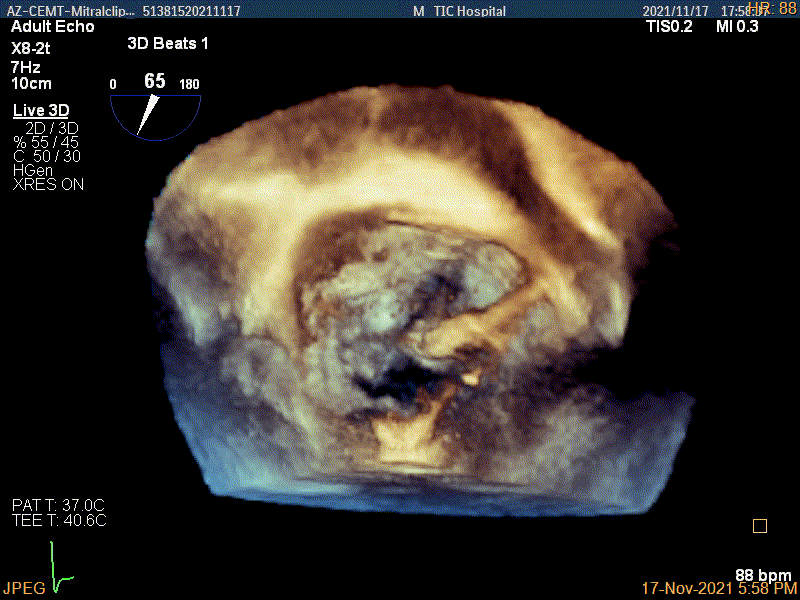

3D-color MV view:源自于交界区的大量反流

3Dcolor证实残余分流主要来源于残余脱垂

3D-color视图下两个夹子间少量残余反流